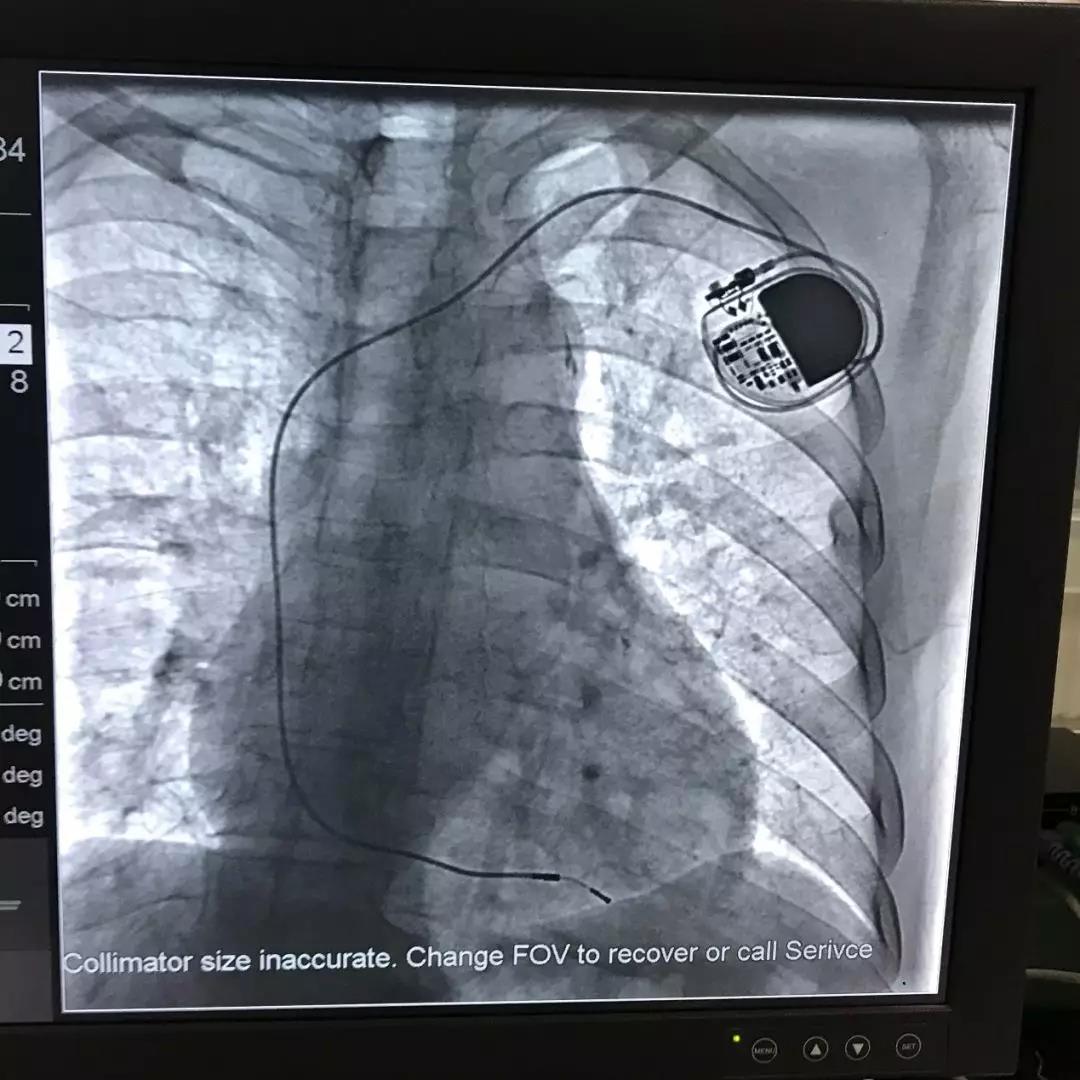

起搏器植入影像